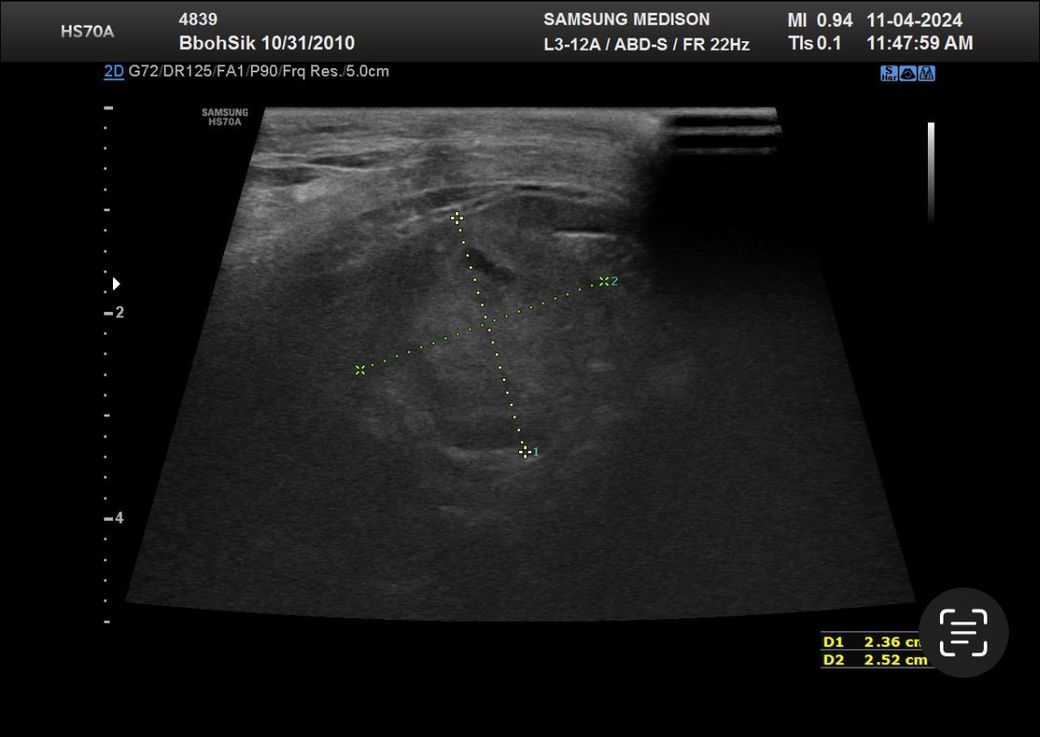

안녕하세요 최근 두군데에서 16살 노령견 복부초음파를 찍었습니다 그런데 두군데에서 서로 다른결과를 말씀하셔서요 한군데는 비장종괴 2.5cm 라고 하시고 한군데에서는 안커지는거보니 비장종괴가 아니라 부신종양이라고 말씀하시던데 뭐가 맞는지 모르겠어서요ㅠ 전에 초음파 찍은게 잇엇던거 같은데 사진 둘중에 뭔지는 잘 모르겟지만 혹시나 아시면 알려주실수있으실까요ㅜㅜ

종괴가 너무 크면 기원 평가에 제한이 있을 수 있으나 2.5cm 의 크기라면 구분하지 못하는 수준은 아닙니다. 이럴때는 영상전공의가 있는 동물병원에 가셔서 초음파 검사를 받고 소견 참조를 하는게 방법입니다. 모든 수의사가 초음파를 다 잘 보는것은 아니기 때문입니다.